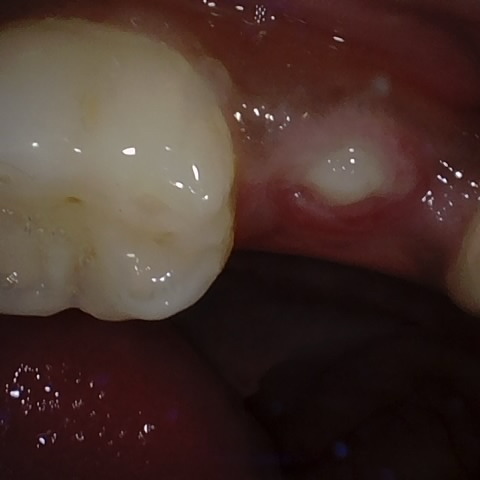

Image 385 / 1715

NHD35761

Annotated as "Good"

Original Image Rendering Image